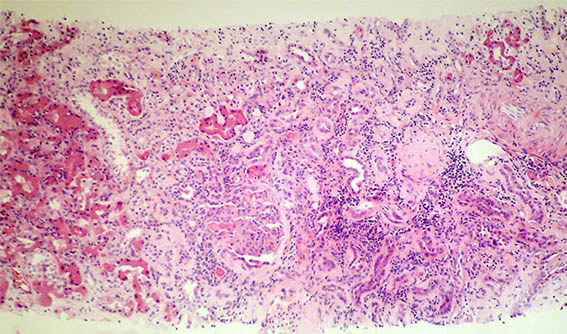

Un hombre de 43 años con insuficiencia renal terminal de causa desconocida, presumiblemente una glomerulopatía, fue trasplantado de donante cadavérico. Función renal adecuada durante los 2 primeros años, con creatinina entre 0,8 y 1,0 mg/dL. Esquema de inmunosupresión: prednisona, tacrolimus y micofenolato, con adecuada adherencia y niveles séricos de tacrolimus en el rango terapéutico esperado. En un control periódico, al tercer año del trasplante, encuentran elevación de la creatinina sérica: 1,4 mg/dL, BUN: 27 mg/dL. Uroanálisis con proteinuria: 300 mg/dL, microhematuria: 15-20 eritrocitos por campo de gran aumento, algunos dismórficos, leucocitos: 6-8; proteinas en orina de 24 horas: 2,6 gramos. Estudios de enfermedades infecciosas negativos, complemento normal. Índices de resistencia en vasos del injerto: normales.

Se hace biopsia del injerto renal, observe las imágenes.

Figura 1. H&E, X100.

Figura 2. H&E, X100.